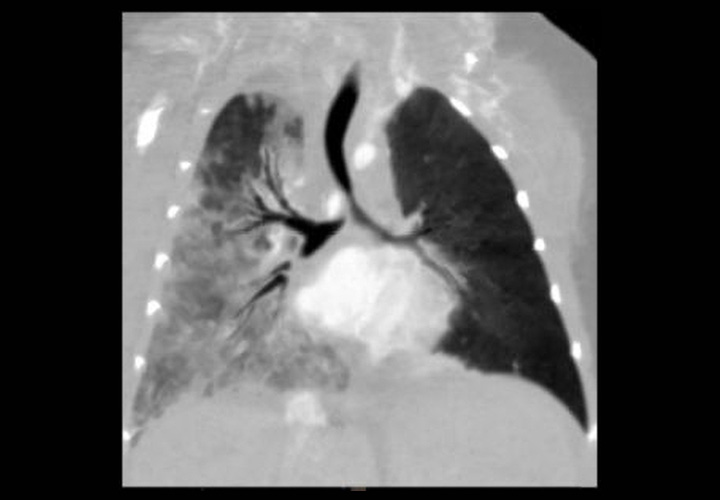

Chest

Case Number :Q-0003

2022-10-29

READ MORE